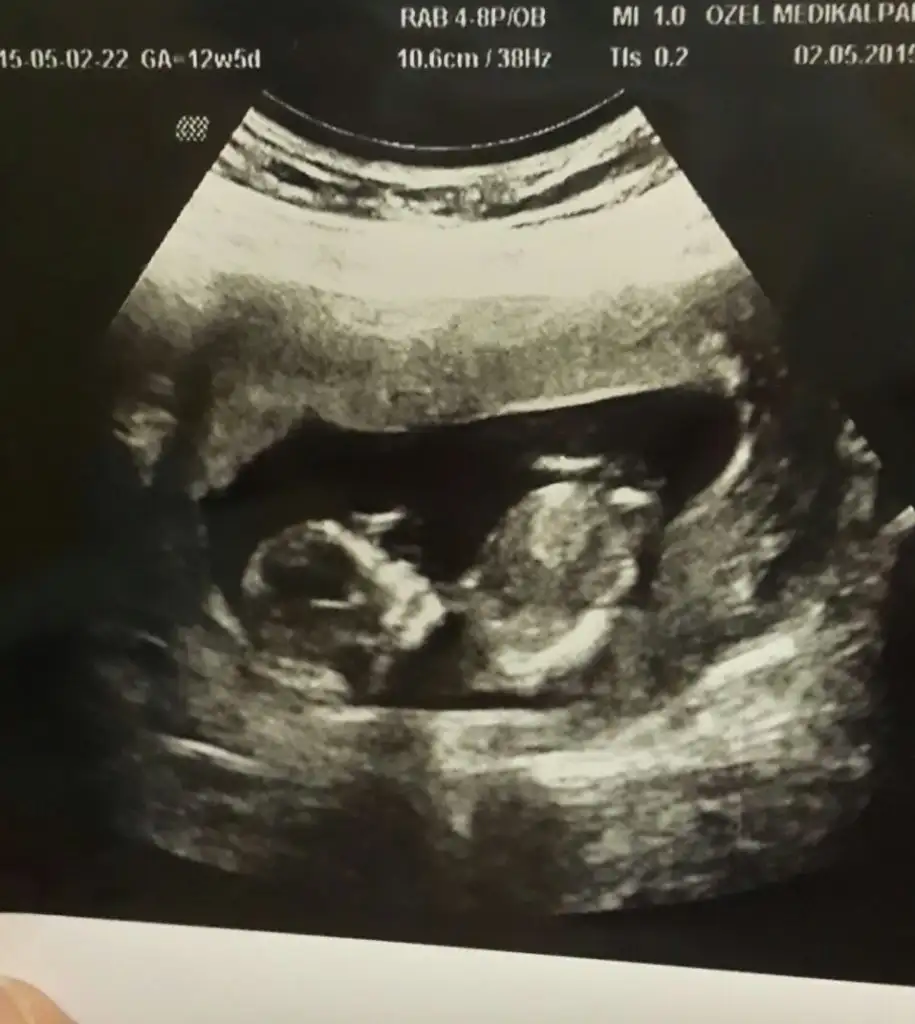

dr soylemeden siz gorun genital nub teorisi ( bebegin cinsiyeti)

Bu bebiste kardeşim in tahmin de bulunabilir misiniz

benimki 12+5 dr kiz gibi ama yanilma olasiligim yuksek dedi. bir ay sonra randevumuz o zaman kesin ogrenirz cok sagol cevabin icin